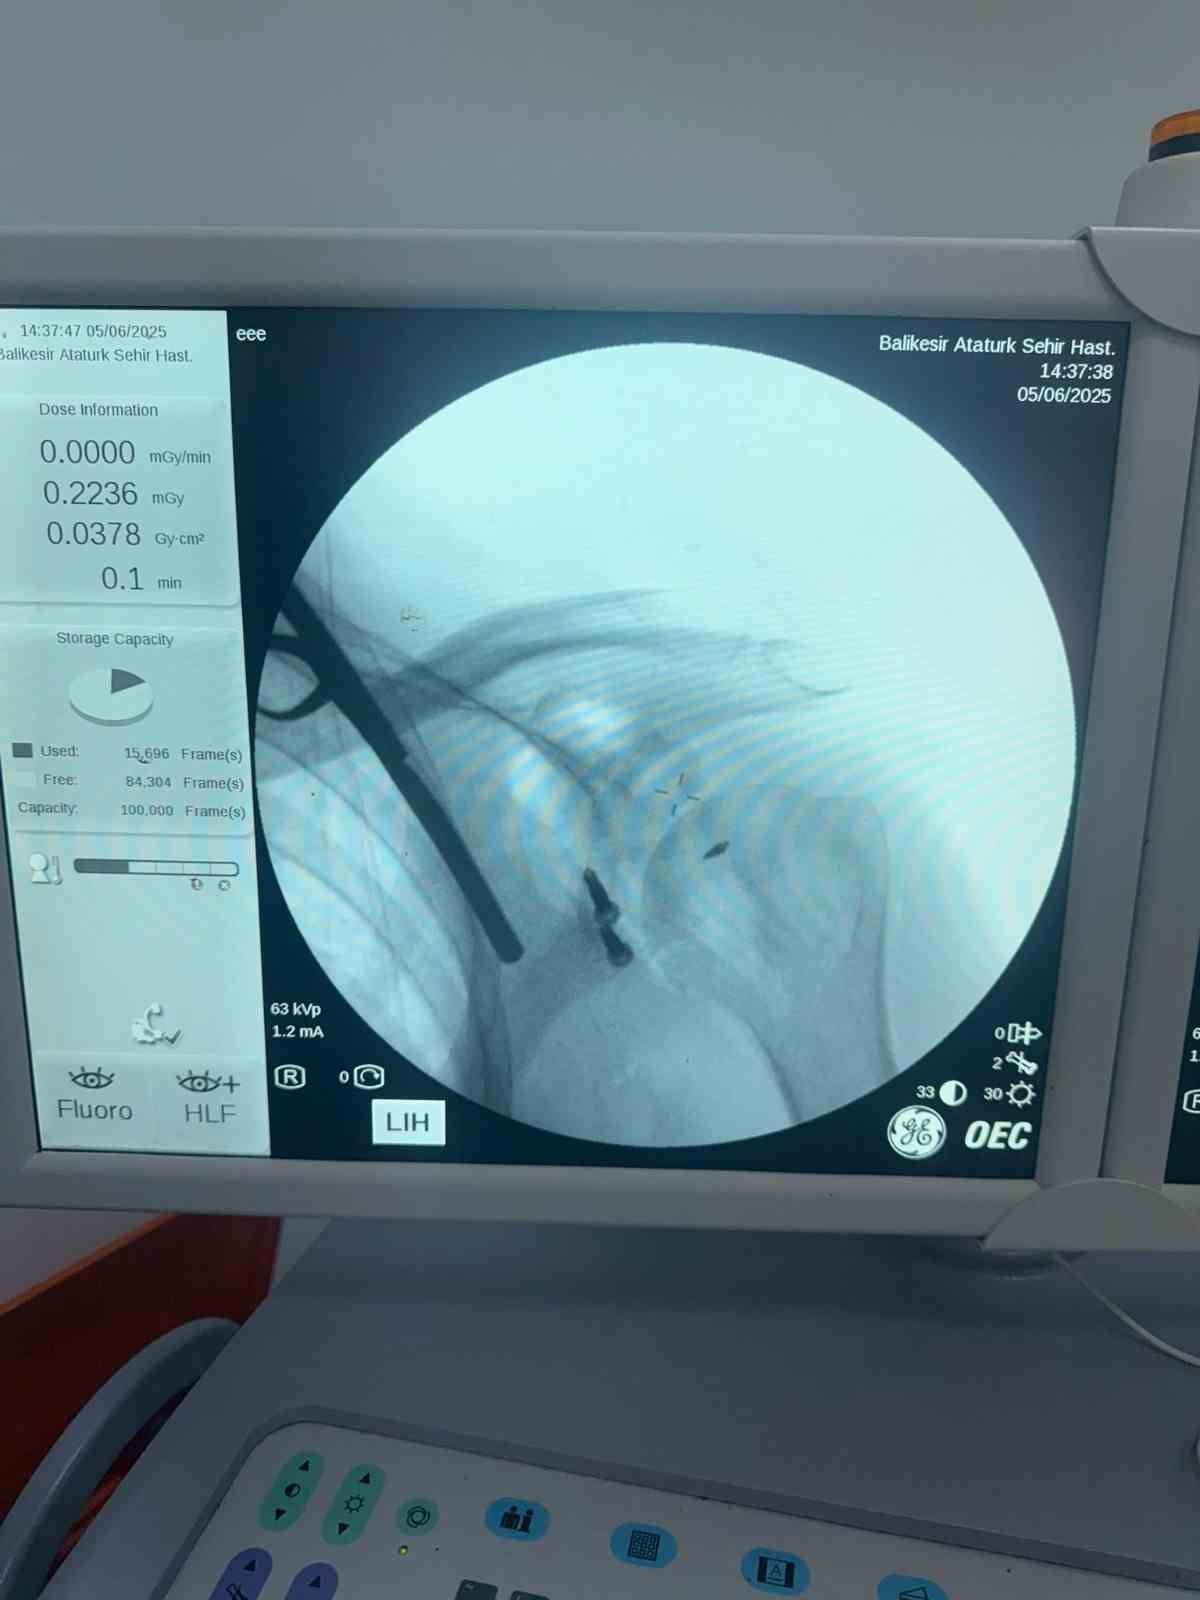

Balıkesir Atatürk Şehir Hastanesinde ilk defa Latarjet Omuz ameliyatı gerçekleştirildi. Balıkesir İl Sağlık Müdürlüğü’nden yapılan basın açıklamasında daha önceden yaklaşık on beş defa omuzu çıkan ve başka İllerde bulunan özel hastanelerde üç defa ameliyat olan hasta şikayetlerinin geçmemesi ve omuzunun tekrar çıkması üzerine Balıkesir Atatürk Şehir Hastanesi Ortopedi ve Travmatoloji Kliniğine başvurdu. Hastanın yapılan muayenesi ve tetkikleri sonucu, hastanın omuz ekleminde aşırı kemik dokusu kaybı mevcut olması sebebiyle "Latarjet omuz ameliyatı" planlandı. Balıkesir de ilk defa uygulanan bu yöntem Doç. Dr. Özgün Karakuş ve Op. Dr. Fatih Işık tarafından başarıyla gerçekleştirildi. Ameliyat sonrası sağlığına kavuşan hasta bir gün sonra taburcu edildi. İl Sağlık Müdürlüğü, "Ameliyat öncesi ve sonrası desteğini esirgemeyen anestezi ekibine, servis, ameliyathane ve yoğun bakım ekibine ve emeği geçen tüm çalışma arkadaşlarımıza teşekkür eder, hastamıza geçmiş olsun dileklerimizi iletiriz" açıklaması yaptı.

Latarjet prosedürü, travmatik omuz çıkığı (çıkıkları) sonrasında kemik hasarı oluşan bir omuza kemiksel stabilizasyon sağlamak için yapılan cerrahi bir prosedürdür. Ameliyat kemik kaybını geri kazandırır ve ön tarafta bir kas askısı sağlar. Latarjet ameliyatı, önemli kemik kaybı nedeniyle omuz instabilitesi (sabit olmayan) yaşayan hastalarda önemli ve sıklıkla önerilen bir omuz ameliyatıdır.